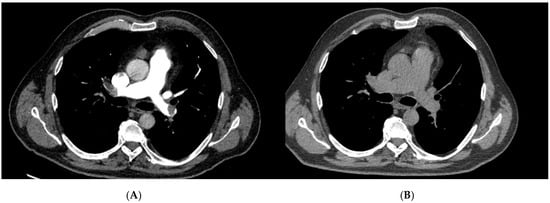

| Localization of PE via CTPA | ||||

| Bilateral central | 79 | 40 | 39 | 0.790 |

| Bilateral segmental | 1 | 1 | 0 | 0.999 |

| Right sided central | 3 | 2 | 1 | 0.5595 |

| Left sided central | 1 | 0 | 1 | 0.999 |

| Left sided segmental | 1 | 0 | 1 | 0.999 |

| Peripheral | 1 | 1 | 0 | 0.999 |

| not specified | 10 | 4 | 6 | 0.506 |